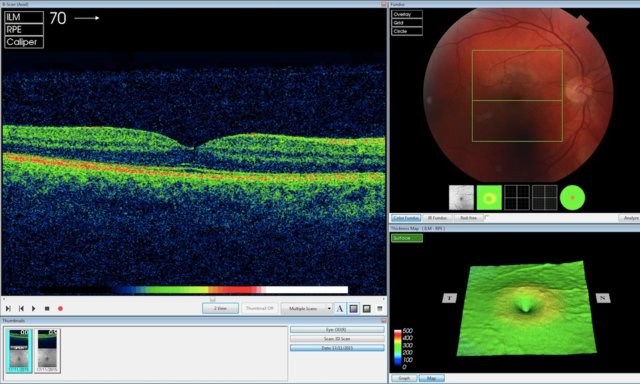

Nói cách khác, AI của DeepMind không giống như một chiếc hộp đen bí mật giúp nhả ra các kết quả. Thiết bị của DeepMind gắn các điểm ảnh lên hình ảnh quét OCT (chụp cắt lớp quang học) mắt để ánh xạ mô mắt và hiển thị các dấu hiệu bệnh cụ thể, từ đó có thể tính toán độ chính xác của những phát hiện và đề xuất của thiết bị trên cơ sở tính số %, ông Suleyman giải thích. “Điều này có ý nghĩa rất lớn”, ông nói thêm.

![]() |

| AI của DeepMind đang phân tích hình ảnh quét OCT (Ảnh DeepMind). |